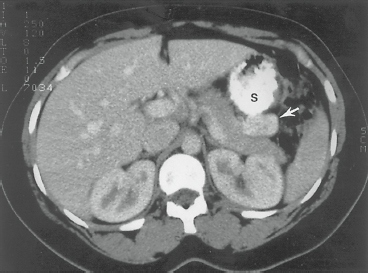

4 The initial imaging technique used to localize a PEN and stage the disease is high-quality multidetector three-dimensional CT.50 The accuracy of CT in detecting primary PENs ranges from 64% to 82% and depends largely on the size of the tumor.51,52 PENs are typically hyperdense (bright) on arterial phases of imaging. Lesions that are obvious during the early arterial phase can become isodense on later phases of imaging. Therefore, a multiphase approach is typically recommended.53,54 CT is useful in assessing size and location of the primary tumor, proximity to visceral vessels, peripancreatic lymph node involvement, and the presence or absence of liver metastases (Fig. 56-1).

Figure 56-1. Computed tomography with oral and intravenous contrast in a patient with biochemical evidence of insulinoma. The neoplasm (arrow) is seen as a contrast-enhancing structure, 3 cm in diameter, in the tail of the pancreas posterior to the stomach (S). (From Yeo CJ. Islet cell tumors of the pancreas. In: Niederhuber JE, ed. Current Therapy in Oncology. St. Louis, MO: Mosby; 1993:272, with permission.)